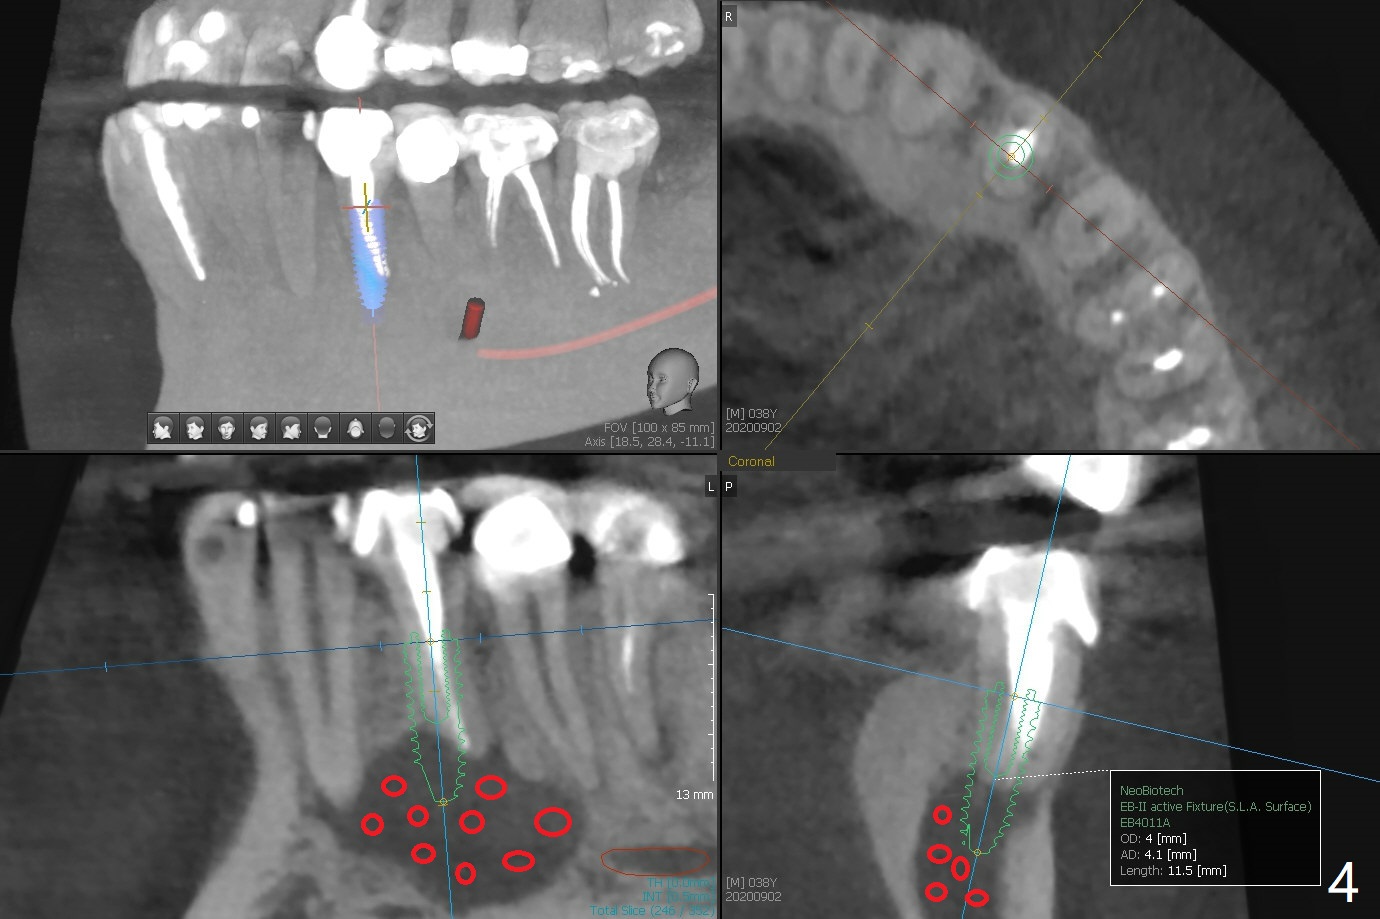

38岁男,十几岁左下4在台湾做根管治疗,八年前外州美国牙医重做根管治疗,他成为我们病人约五年,根尖阴影一直存在,由于无症状,没有引起重视。不过近半年主诉左下唇偶尔麻木,全景片似乎显示左下4根尖阴影相当大,今天CT检查证实这一点(图一),仿佛是根尖囊肿;右下前磨牙区多生牙(*),右上8颊侧也有一个多生牙(图二:8')。虽然病人恐惧手术,但是他不愿意去看专家。尽管囊肿大,累及邻牙,尤其是左下三(图三(可能死髓,Endo Ice; Electric Pulpal Tester;根管治疗)),但是首先做根尖半月形切口,做比较大的根尖切除术,试图刮治囊肿。如果手术当时刮治不全,拔除患牙,增加视野,彻底刮治,填入大量粘性骨块(图四:红圆圈),覆盖PRF膜,缝合,牙周敷料。由于工作需要,病人说他不能没有牙,如果可能,做即刻植牙(图四:绿色),即刻无咬合修复。准备Collagen or Osteogen Plugs,压迫止血。